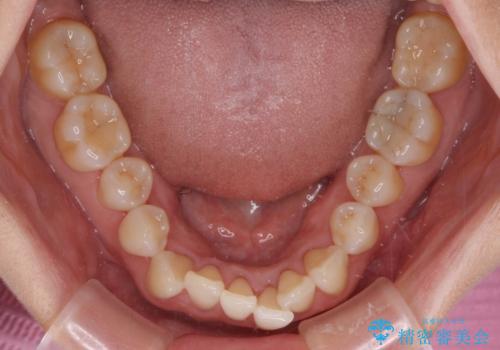

前歯のスペースが気になる インビザラインによる矯正治療

- 前歯の上下スペースによる食べにくさを気にして来院された患者様です。

インビザラインにより上下の前歯の隙間を閉じていくこととしました。

舌の突出癖があると上下前歯にスペースが開くため、矯正治療を機会に舌癖を改善するトレーニングを行ってもらい、矯正治療後の後戻りを防止するように指導しています。